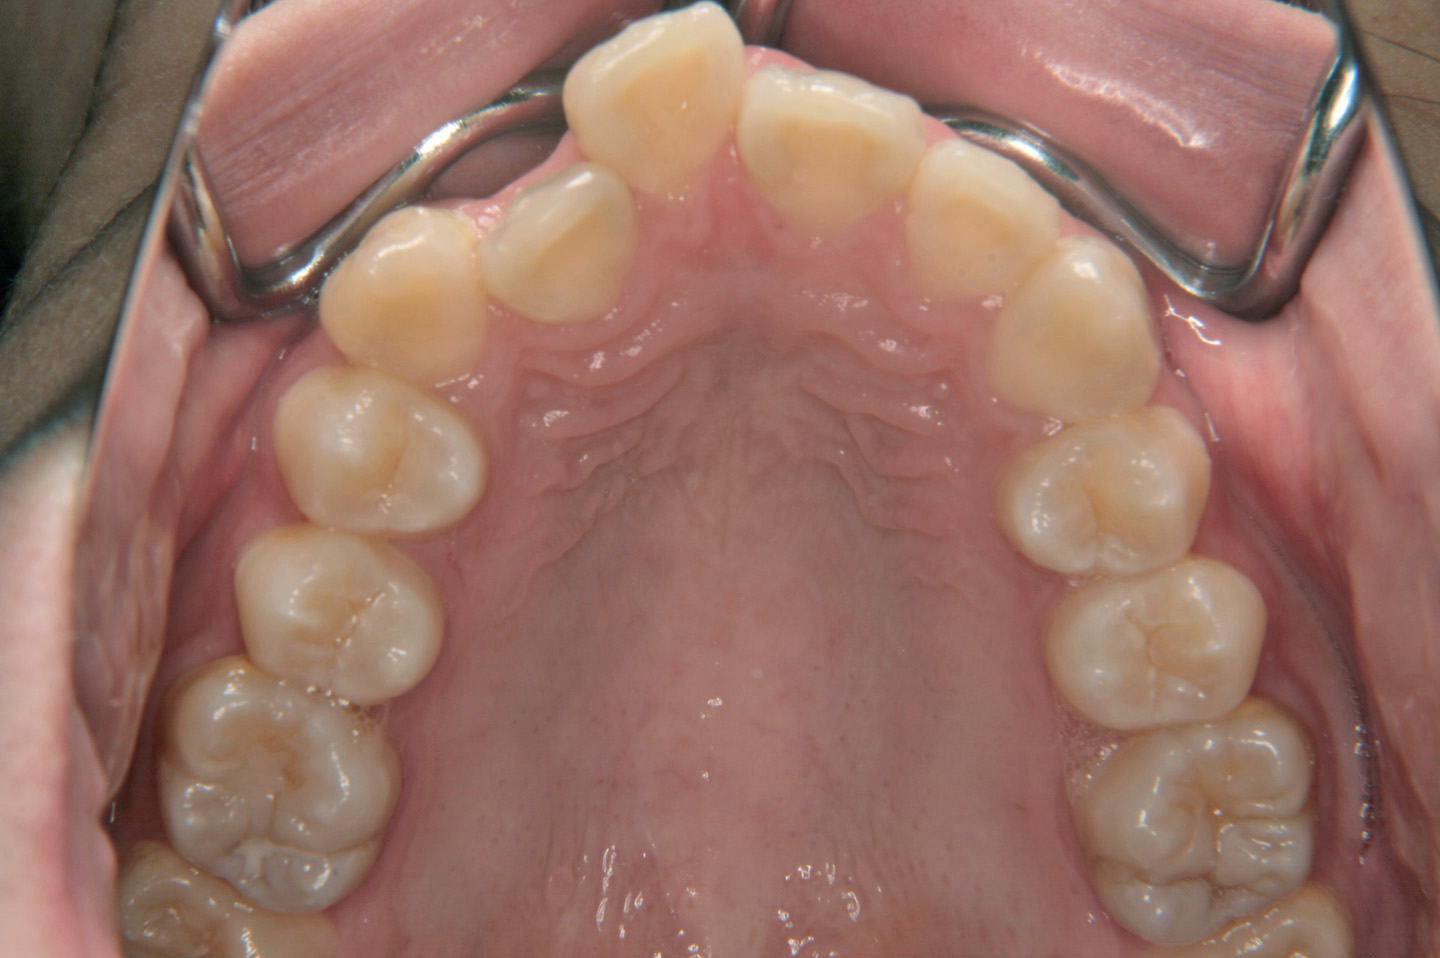

出っ歯を気にされて来院された成人の女性です。叢生と上顎前突の改善のため上顎小臼歯を抜歯させていただいて、上顎は裏側からの装置(リンガルブラケット)で歯並びを整えました。ボンデッドワイヤーとエシックス併用した保定に移行しております。

初診時

動的治療終了時